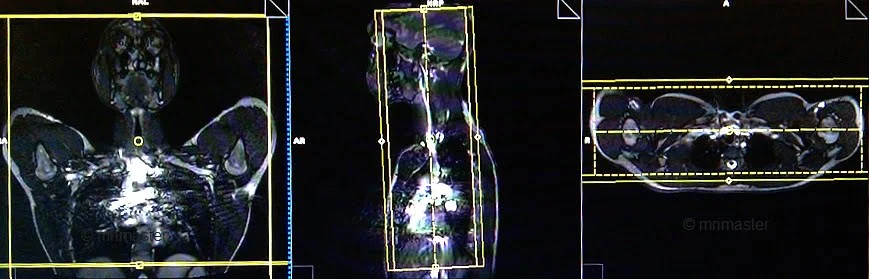

T1 flash dynamic 3D coronal .9mm - 1.1mm post-contrast 2 measurements

Plan the coronal slices on the sagittal plane; angle the positioning block parallel to the carotid arteries and veins (alternatively, make it parallel to the cervical spine). Check the positioning block in the other two planes. Provide an appropriate angle in the axial plane (parallel to the right and left shoulder joint). The slices must be sufficient to cover the subclavians from the anterior chest wall to the spinous process of the vertebrae. The Field of View (FOV) must be large enough to cover both shoulder joints. Phase oversampling and slice oversample must be used to avoid wrap-around artifacts. Instruct the patient to hold their breath during image acquisition (in our institution, we instruct patients to breathe in and out twice before the “breath in and hold” instruction). It is highly advisable to use Parallel Acquisition Technique to reduce the scan time (the scan time should be less than 16 seconds to get the best results).

MRA(magnetic resonance angiography) Subclavians planning of coronal 3D arm down 2 - MRI

Plan the coronal slices on the sagittal plane; angle the positioning block parallel to the carotid arteries and veins (alternatively, make it parallel to the cervical spine). Check the positioning block in the other two planes. Provide an appropriate angle in the axial plane (parallel to the right and left shoulder joint). The slices must be sufficient to cover the subclavians from the anterior chest wall to the spinous process of the vertebrae. The Field of View (FOV) must be large enough to cover both shoulder joints. Phase oversampling and slice oversample must be used to avoid wrap-around artifacts. Instruct the patient to hold their breath during image acquisition

MRA(magnetic resonance angiography) Subclavians planning of coronal 3D arm up 5 - MRI